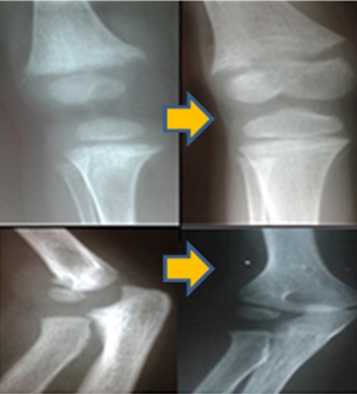

Imágenes: radiografías de huesos largos  con signos compatibles con raquitismo (osteopenia, epífisis en forma de copa, refuerzo de la cortical de los huesos largos, poco desarrollo de la epífisis y metáfisisb (Figura 1). Edad ósea retrasada en más de un año. Ecografía renal con nefrocalcinosis bilateral, riñones de tamaño normal (Figura 2). Sin litiasis.

Figura 1. Radiografías de huesos largos al inicio del seguimiento (lado izquierdo) y posteriores al tratamiento (lado derecho)

La paciente fue evaluada por un período de 2 años y 6 meses. A corto plazo logró mejoría clínica (velocidad de crecimiento y sintomatología osteomuscular), de laboratorio: fosfatemias 2,6 mg/dl, normalización de la FAL (siempre elevada en los raquitismos, lo cual es paralelo a la actividad osteoblástica), de la calciuria y vitamina D; radiológica (Figura 2) como de la nefrocalcinosis. No presento litiasis, proteinuria ni caída del filtrado glomerular.